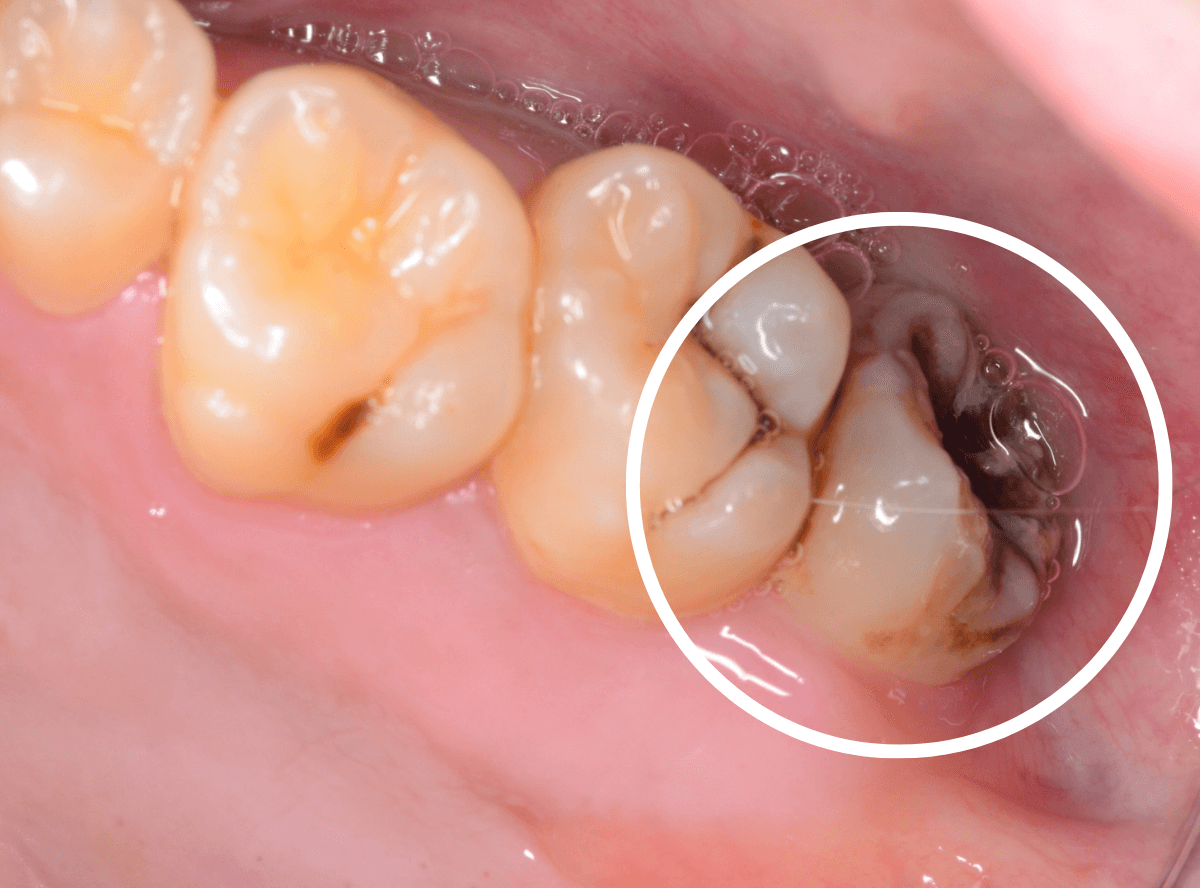

ここでは、比較的簡単なおやしらずの抜歯の例を中心にご紹介します。

このようなおやしらず、あなたはありませんか?